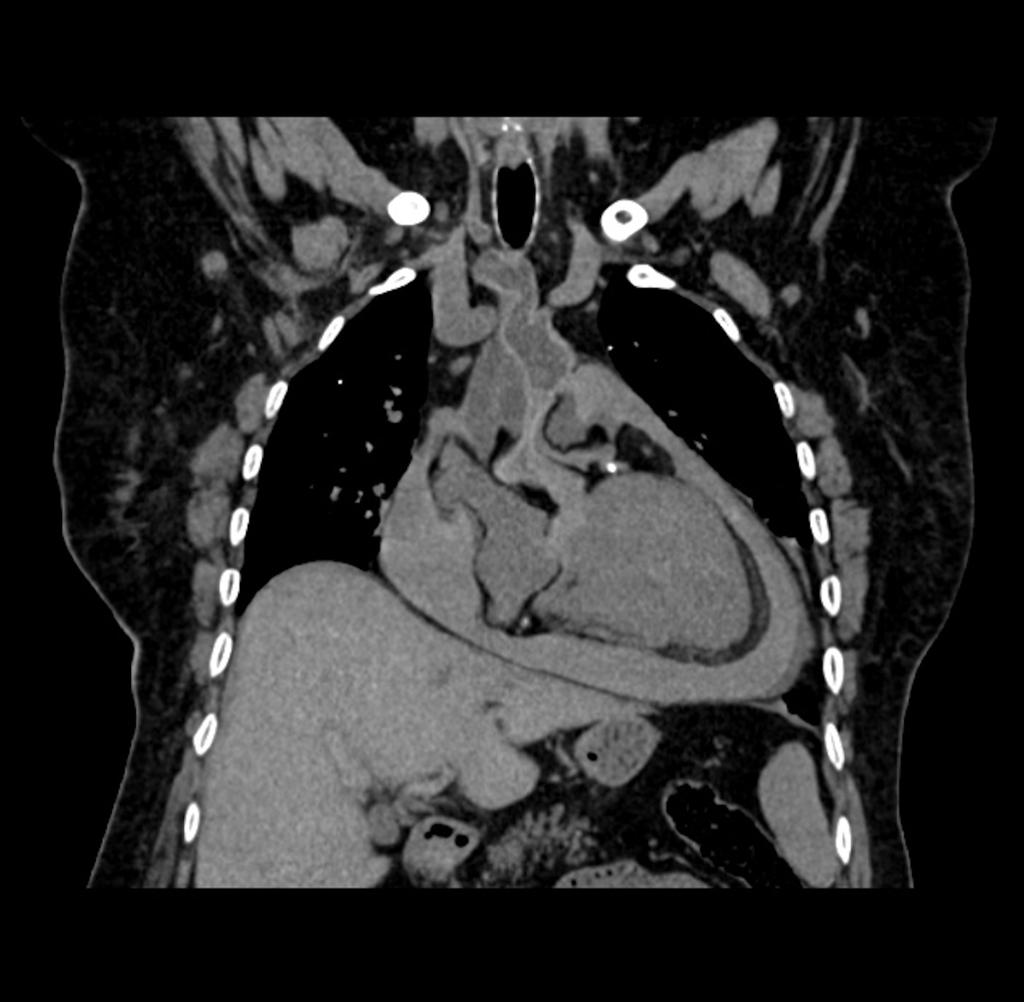

Gepubliceerd: Week 25 - 2020 212 deelnemers Een 84-jarige vrouw wordt dood aangetroffen in haar bed. Uit de hetero-anamnese blijkt dat ze 3 dagen ervoor had geklaagd over nachtelijke pijn op de borst, die vanzelf minder was geworden. Wat is uw diagnose? Antwoord hemopericard normale postmortale bevinding pericarditis constrictiva cardiaal lymfoom Antwoord controleren